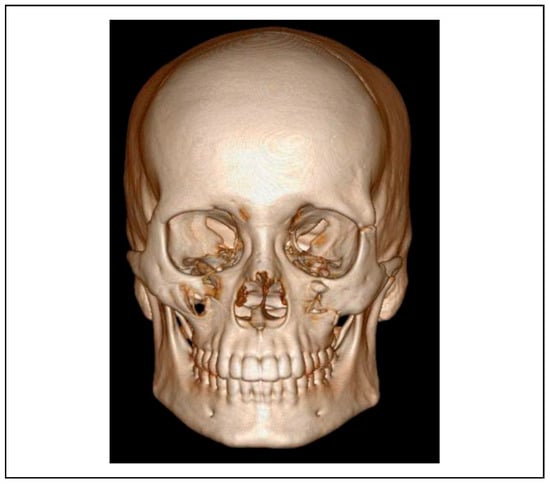

The protocol for this study included imaging in the form of a preoperative and postoperative 3D computed tomography scan with reconstruction of the maxilla and mandible to interpret the diagnosis for all subjects. A standard CT scanner (GE ADW 4.5 workstation) was used with a 0.60 mm slicing mechanism depicting axial, coronal and sagittal sections [4] (Figure 1 and Figure 2). The inter-fracture distance of the fractured infraorbital rim were measured in 3 dimensions (antero-posterior, medio-lateral and supero-inferior) and compared pre and postoperatively. All subjects of the study group underwent an ultrasonographic examination intraoperatively using a mobile ultrasound machine (SONOSITE S-ICU) with a standard transducer (linear probe—L14-5) in variable frequencies ranging from 6 to 10 MHz. Images were depicted with a 70% gain and 60% depth of focus.

Figure 1.

Preoperative CT scan—3D.

Figure 2.

Postoperative CT scan—3D.